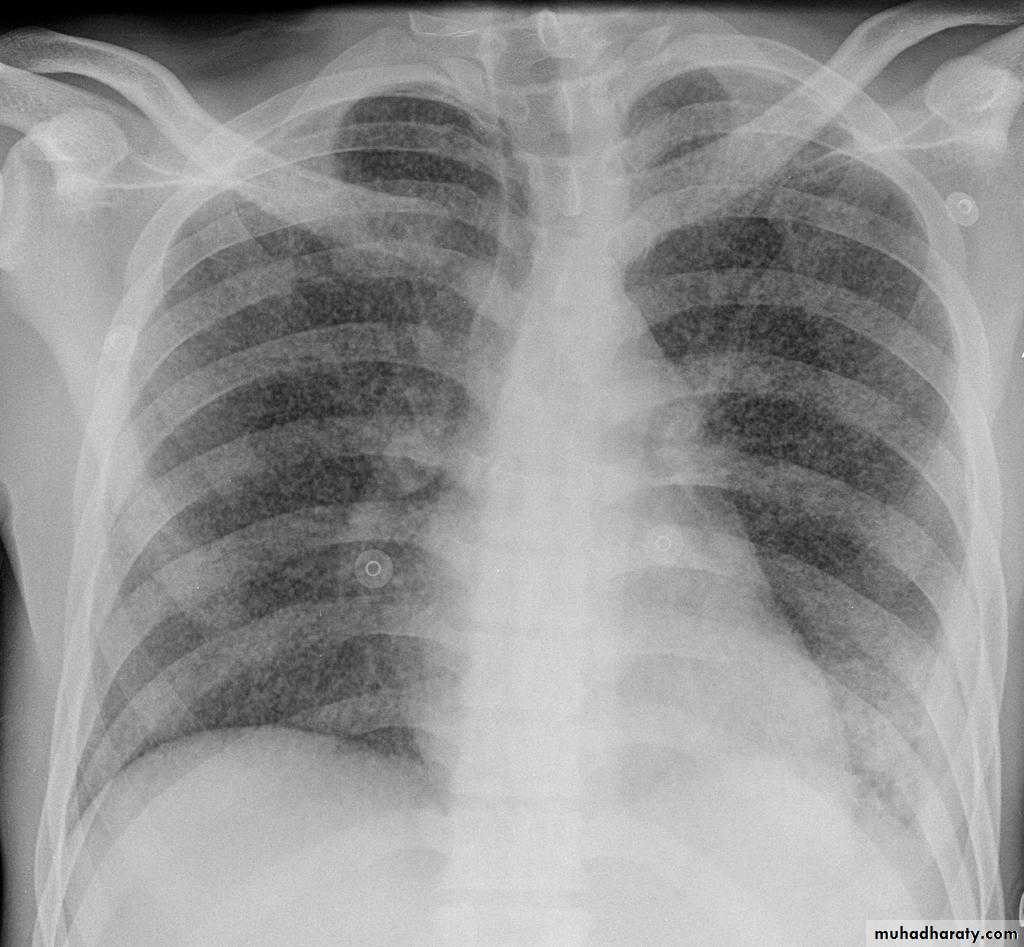

Plain radiographChest radiographs are the most commonly used examination to assess for presence of a pleural effusion, however it should be noted that on a routine erect chest x-ray as much as 250-600 ml of fluid is required before it becomes evident 6. A lateral decubitus film is most sensitive, able to identify even a small amount of fluid. At the other extreme, supine films can mask large quantities of fluid.

Both PA and AP erect films are insensitive to small amounts of fluid. Features include:

blunting of the costophrenic angle

blunting of the cardiophrenic angle

fluid within the horizontal or oblique fissures

eventually a meniscus will be seen, on frontal films seen laterally and gently sloping medially (note: